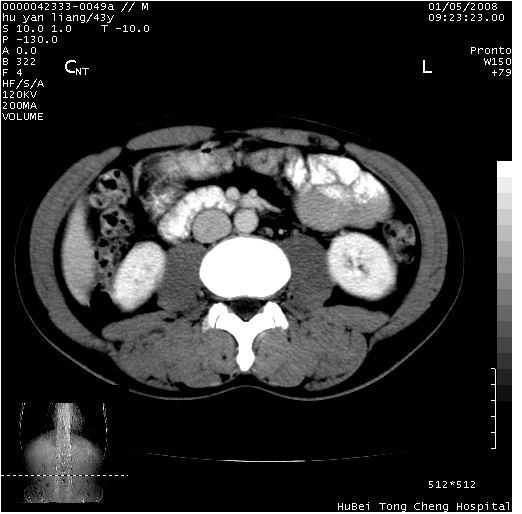

患者 男,43岁。右上腹不适1年余。既往有“肝右叶肝脓肿”病史,经保守治疗后痊愈。

b超提示:1)肝右叶肝内胆管结石。2)肝右叶占位性病变待排。

上中腹部ct轴位平扫+增强扫描(层厚10mm,螺距1.0,重建间隔10mm),图像如下:

肝右上叶偏后方较大团片状钙化灶,支持:肝脓肿后遗改变!

肝右叶后段团块状钙化灶,结合病史考虑肝脓肿痊愈后表现。